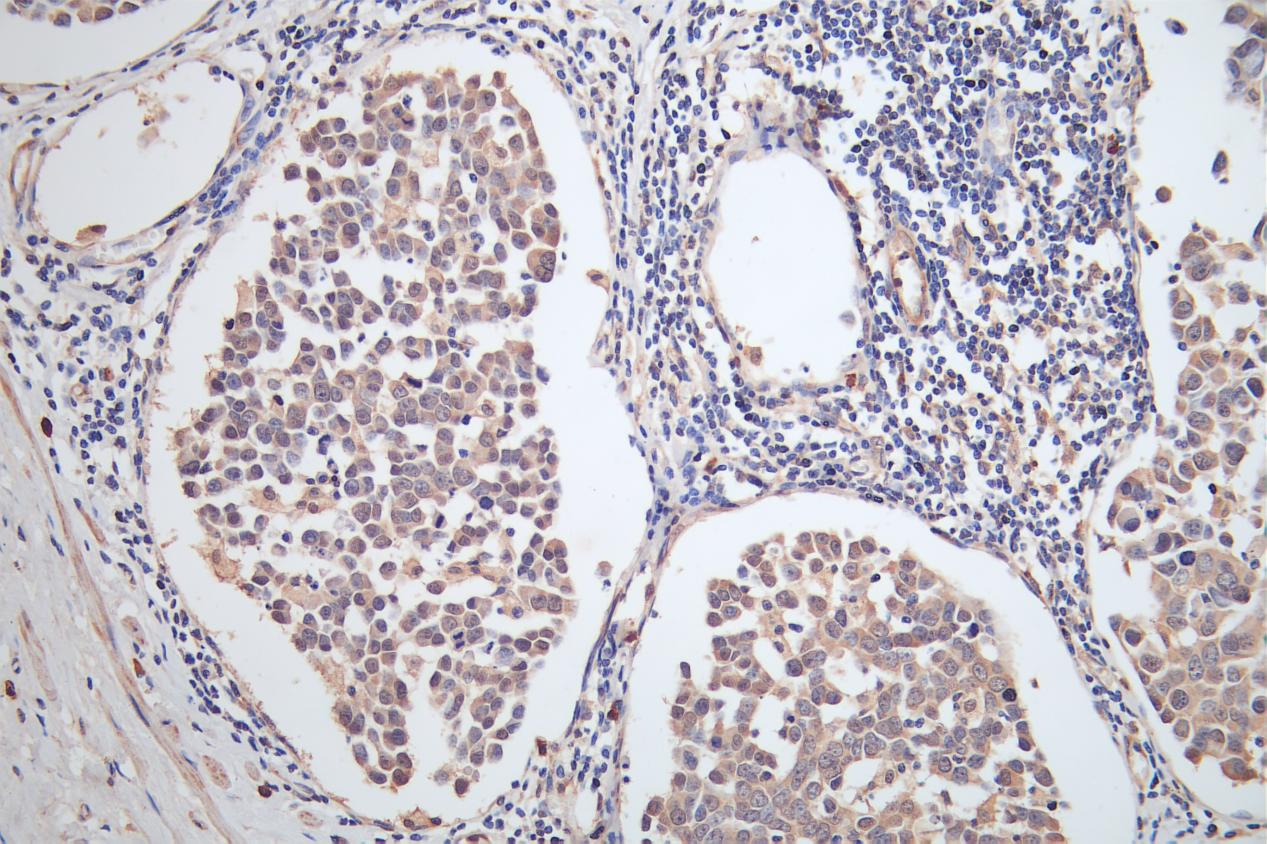

• IHC image of CSB-PA740936ESR2HU diluted at 1:100 and staining in paraffin-embedded human gastric cancer performed on a Leica BondTM system. After dewaxing and hydration, antigen retrieval was mediated by high pressure in a citrate buffer (pH 6.0). Section was blocked with 10% normal goat serum 30min at RT. Then primary antibody (1% BSA) was incubated at 4°C overnight. The primary is detected by a Goat anti-rabbit polymer IgG labeled by HRP and visualized using 0.05% DAB.